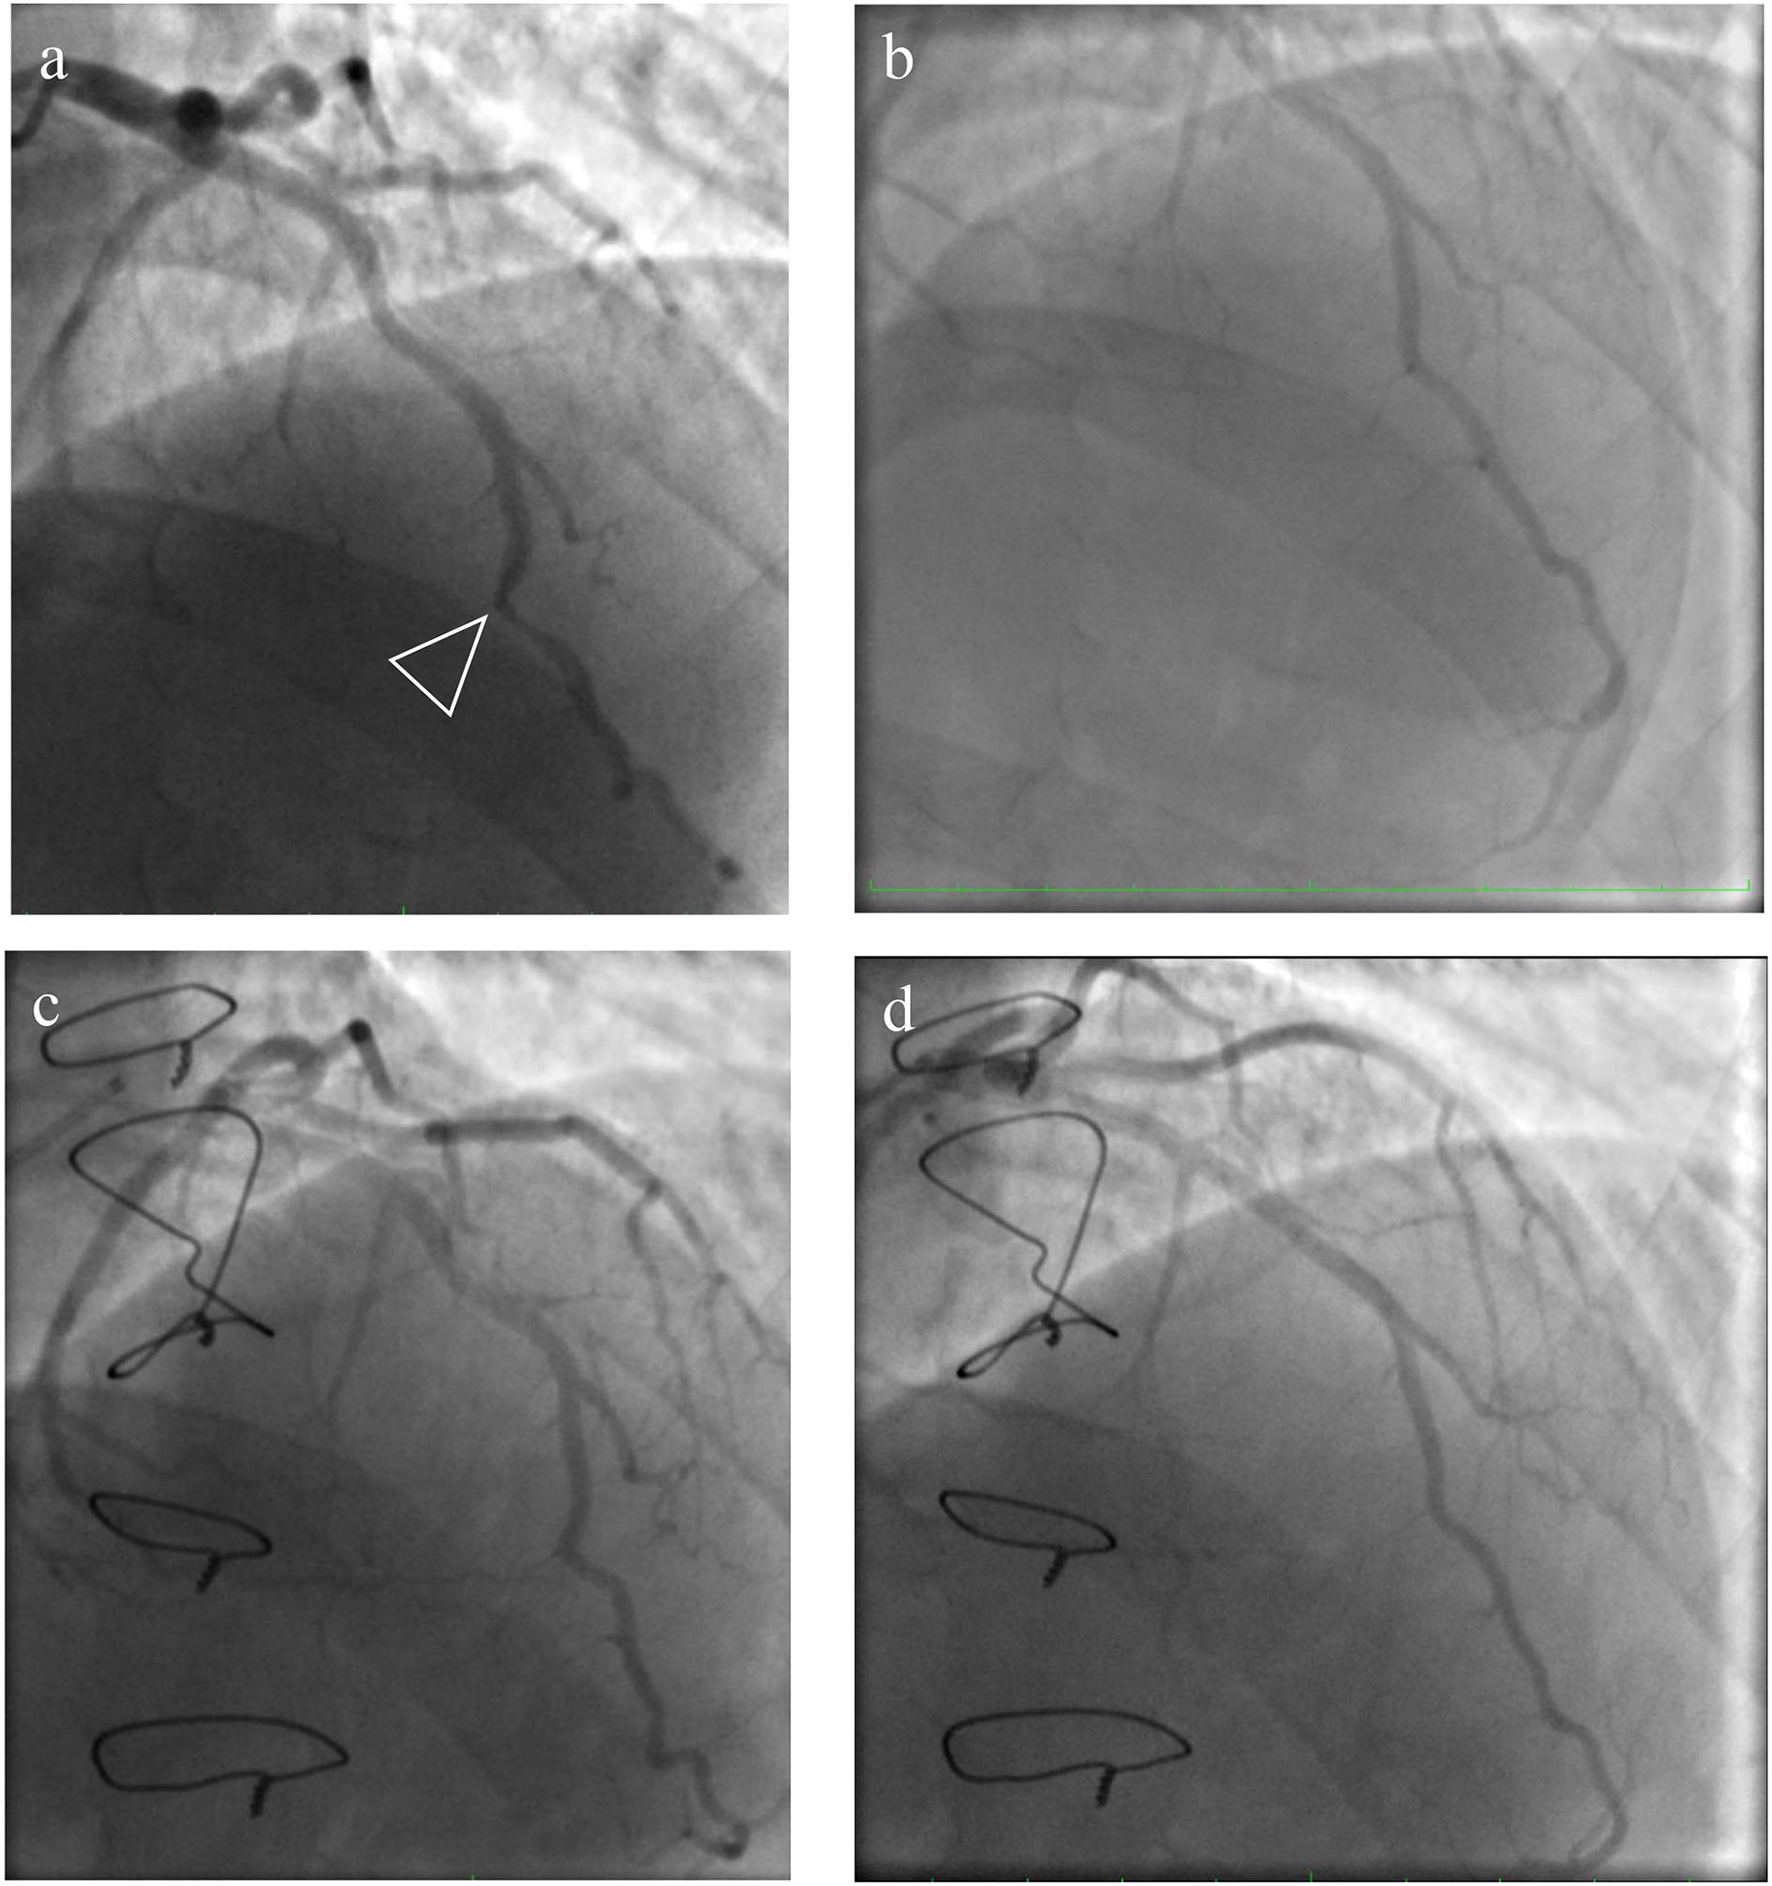

A 36-year-old man was referred to the Almazov National Medical Research Centre with a history of progressive heart failure (NYHA III functional class), chest pain, and the presence of severe pulmonary hypertension (PH) according to a transthoracic echocardiographic evaluation (TTE). The patient had a documented history of acute pulmonary embolism with a delayed diagnosis and initiation of anticoagulant therapy. TTE showed right atrial and right ventricle dilatation with preserved right ventricle function, left ventricle size, and function, and the estimated pulmonary artery systolic pressure was 120 mmHg (Table 1). Chest dual-energy CT-angiography and pulmonary angiography confirmed CTEPH (level II according to San Diego pulmonary endarterectomy disease levels) (Figures 1a,b). Right heart catheterization (RHC) defined precapillary PH: mean pulmonary artery pressure (PAP) of 59 mmHg, a pulmonary capillary wedge pressure (PCWP) of 13 mmHg, and a pulmonary vascular resistance of 7,98 Wood units. Riociguat treatment was started. Thrombophilia markers were tested, and antiphospholipid antibody syndrome was revealed as the main CTEPH risk factor. There were no data in favor of systemic lupus erythematosus or other systemic connective tissue diseases. Due to chest pain, selective coronary angiography was performed, and the LAD-MB was revealed. The length of the LAD-MD was ~25 mm, with left anterior descending artery stenosis in the systole reaching 70% (Figures 2a,c, arrowhead).

Figure 1. Pre- and post-operative selective pulmonary angiography. (a) Selective pulmonary angiography of the right pulmonary arteries identified: eccentric and extended stenoses in the segmental arteries A 1, 2, 4, 5, 6, 7, 8, and occlusion of A 3, 9, 10; (b) left pulmonary artery: occlusion of the upper lobe branch, roughness of the contours of the lower lobe branch, and eccentric and extended stenoses in the segmental arteries of the lingual segment and lower lobe; (c,d) selective pulmonary angiography after surgery.

Figure 2. Pre- and post-operative view of coronary angiography. (a) An intramyocardially located section of the left anterior descending artery (LAD) in the middle third with stenosis in the systole up to 60–70%; (c) the systolic phase of the LAD-MB after the surgery; (b,d) the diastolic phase of the LAD-MB before and after the operation.

The patient's health significantly improved and had no dyspnea at 8 months of follow-up. Selective pulmonary angiography demonstrated preserved blood flow over all pulmonary fields. No stenosis and occlusion of segmental branches were visible (Figures 1c,d). Coronary angiography found no local stenosis of the LAD artery (Figures 2c,d). The control RHC showed normalization of pulmonary hemodynamics with a reduced mean pulmonary artery pressure of 22 mmHg and an RVR of 1.7 WU (Table 2).